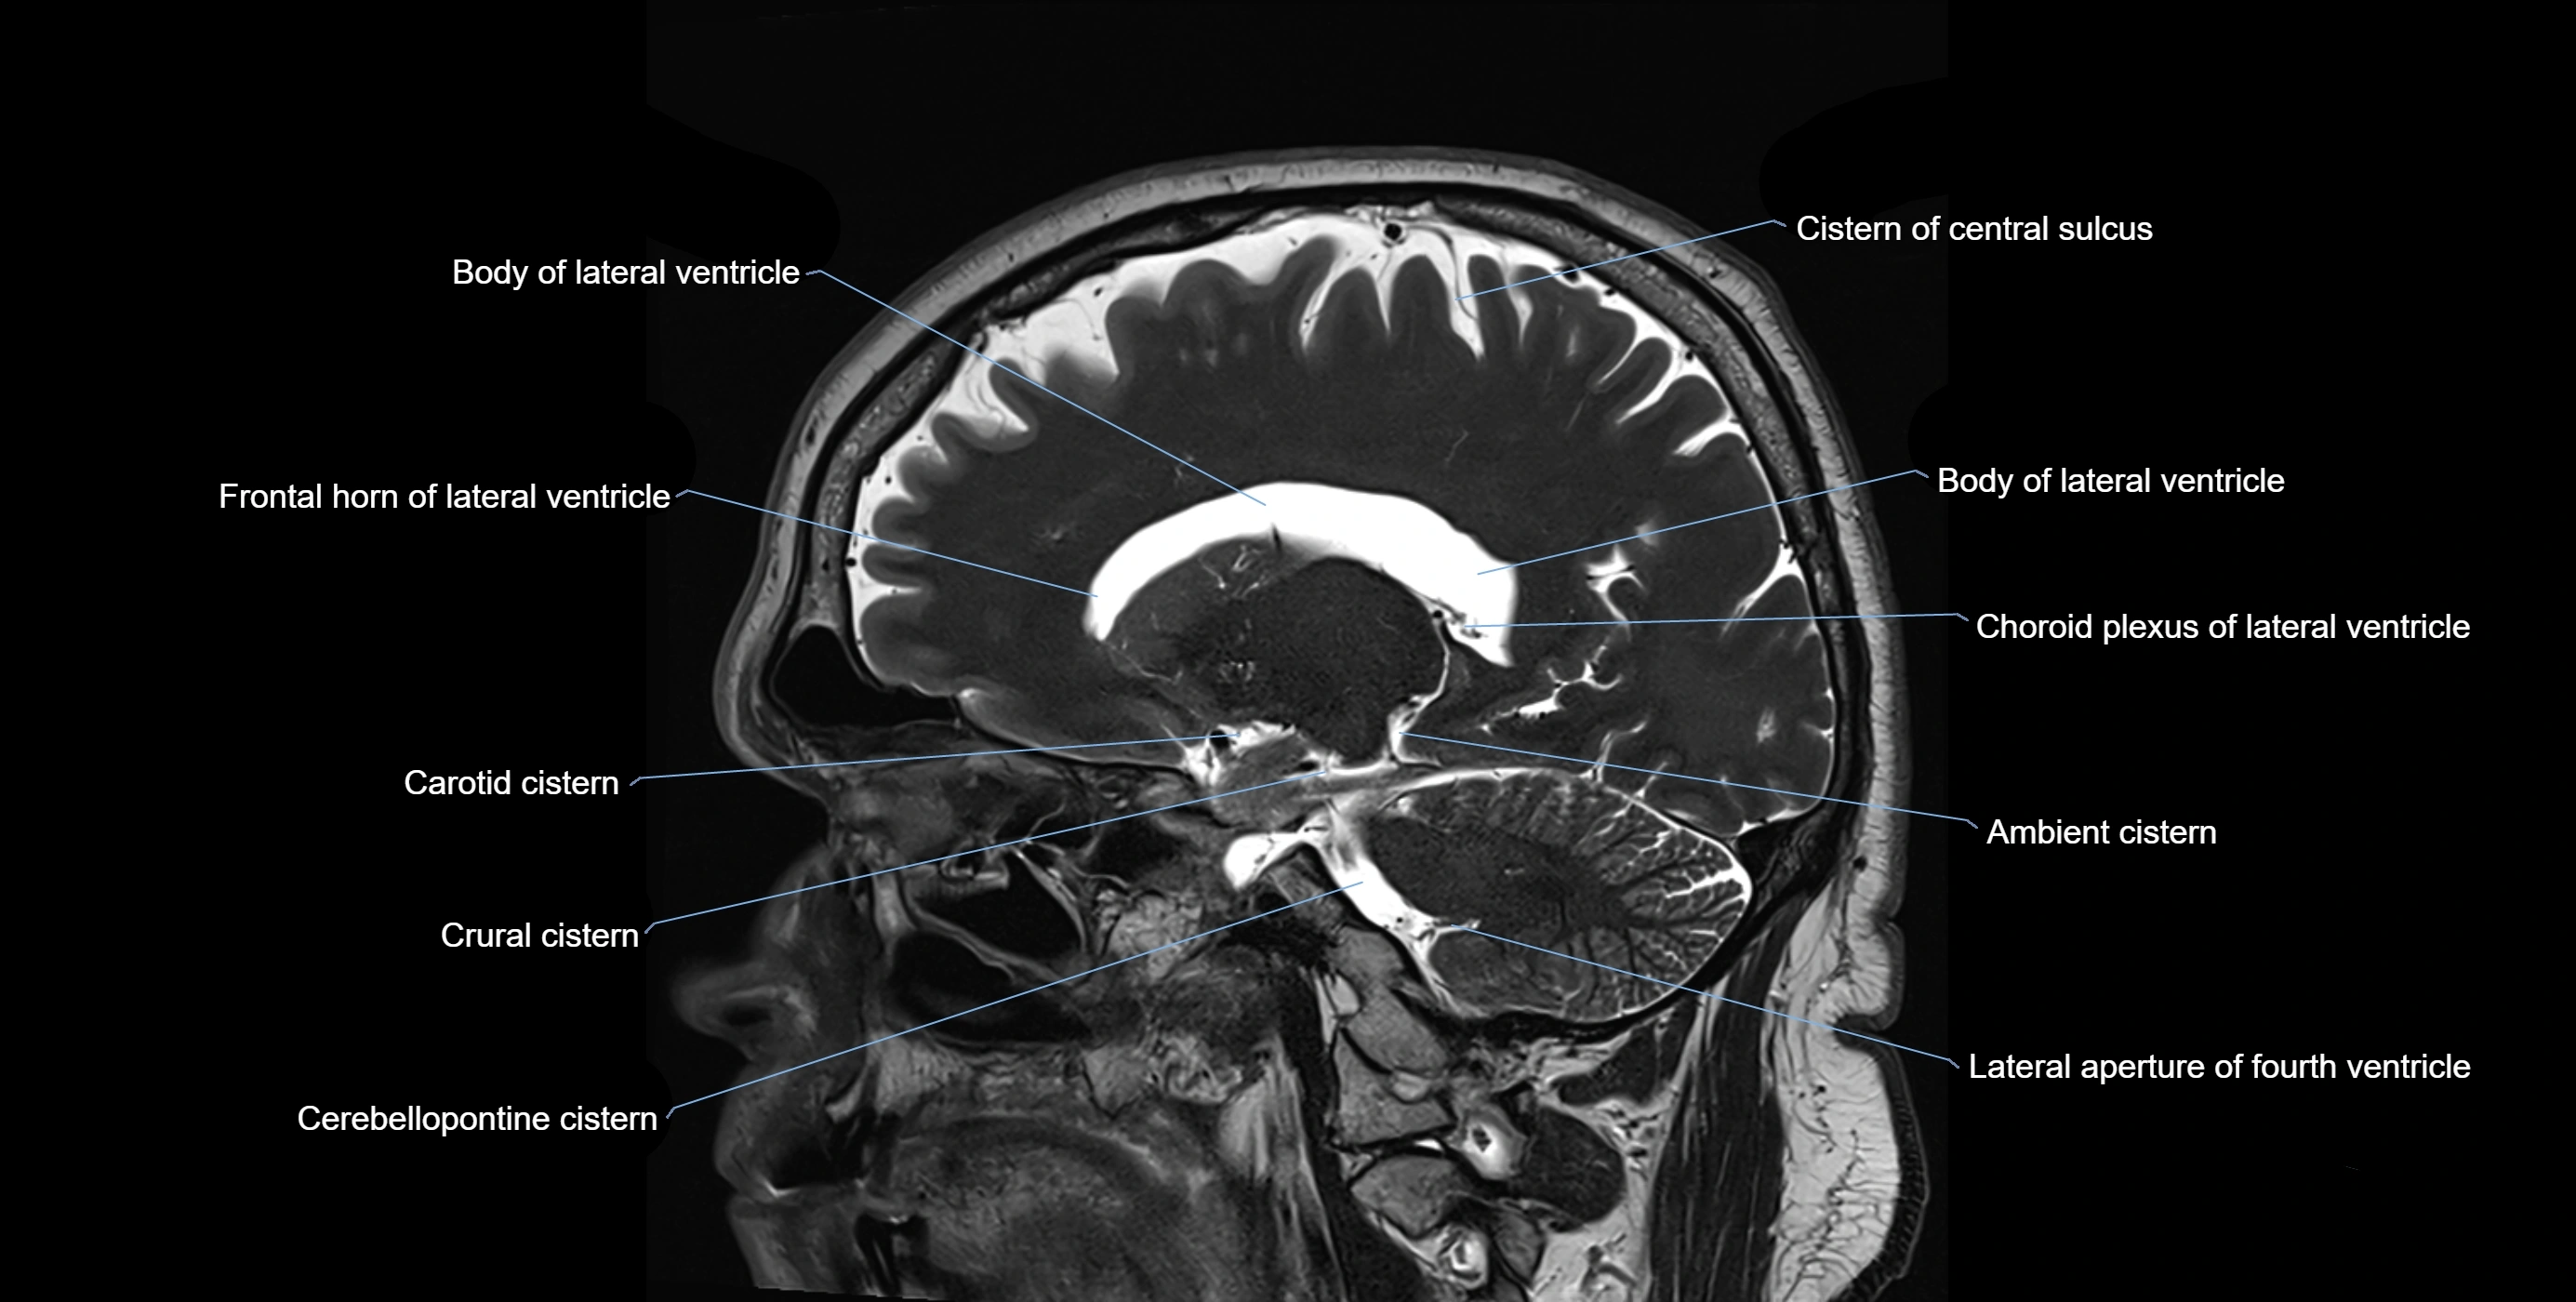

Ambient cistern

The ambient cistern is a paired, narrow, and elongated subarachnoid space located bilaterally along the lateral aspect of the midbrain. It serves as a conduit between the interpeduncular cistern anteriorly and the quadrigeminal cistern posteriorly. This cistern houses critical neurovascular structures, including parts of the posterior cerebral artery, superior cerebellar artery, trochlear nerve (cranial nerve IV), and the basal vein of Rosenthal. It plays an important role in the circulation of cerebrospinal fluid (CSF) and provides an anatomical corridor for various vessels and nerves passing around the midbrain.

MRI images

image